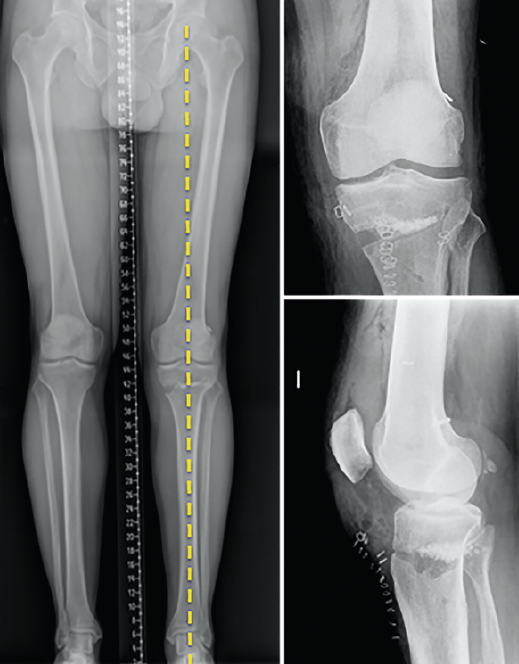

Other tests that contribute to the diagnosis are stress valgus radiographs (local anesthesia infiltration is advised in order not to underestimate the test), magnetic resonance imaging (MRI) and arthroscopic exploration (Figure 1).

[[{"fid":"4710","view_mode":"default","fields":{"format":"default","alignment":""},"type":"media","field_deltas":{"1":{"format":"default","alignment":""}},"link_text":null,"attributes":{"class":"media-element file-default","data-delta":"1"}}]]

Other diagnostic tests are radiographs under stress varus conditions. We can find indirect radiological signs such as Segond fracture and the arcuate sign. MRI is of great help. Gelber et al. recently reported that over 80% of a group of world experts in the treatment of posterolateral angle injuries agree on the usefulness of MRI in the diagnosis of these lesions(17). Lastly, arthroscopy can offer additional information in the surgical cases (Figure 2).

[[{"fid":"4711","view_mode":"default","fields":{"format":"default","alignment":""},"type":"media","field_deltas":{"2":{"format":"default","alignment":""}},"link_text":null,"attributes":{"class":"media-element file-default","data-delta":"2"}}]]